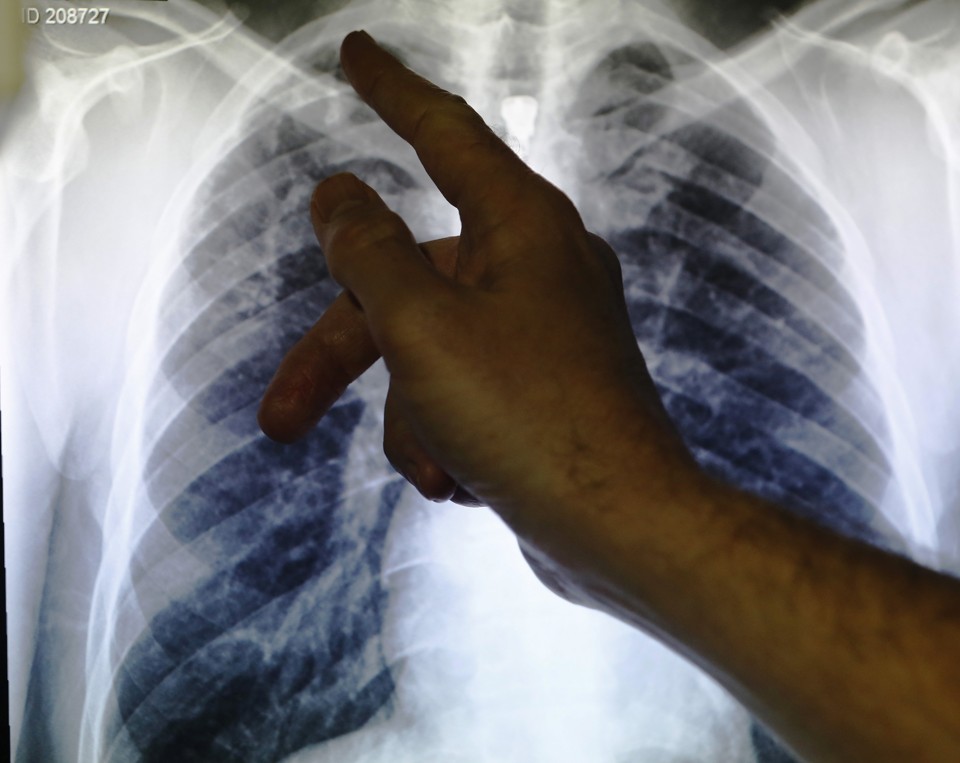

From www.istockphoto.com

Chest X Ray Patient With Tuberculosis Stock Photo Download Image Now Is Tb Deadly If Untreated Tb most often affects your lungs, but can also affect other organs. Cdc estimates up to 13 million people in the united states live with inactive. tuberculosis (tb) can be deadly if a person does not receive treatment. tb disease is usually treated with antibiotics and can be fatal without treatment. tuberculosis is a bacterial infection that. Is Tb Deadly If Untreated.